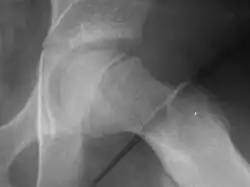

Młodzieńcze złuszczenie głowy kości udowej

Młodzieńcze złuszczenie głowy kości udowej (MZGKU, łac. epiphyseolysis capitis femoris, ang. slipped capital femoral epiphysis, SCFE) – choroba ogólnoustrojowa o nieznanej etiologii, w której przebiegu zaburzona jest budowa chrząstek nasadowych. Jest jedną z najczęstszych chorób stawu biodrowego w wieku dziecięcym. Leczone jest zawsze operacyjnie.

Objawy w RTG:

- objaw Kleina-Trethowana (objaw stycznej): styczna poprowadzona wzdłuż górnego brzegu szyjki nie odcina fragmentu głowy kości udowej